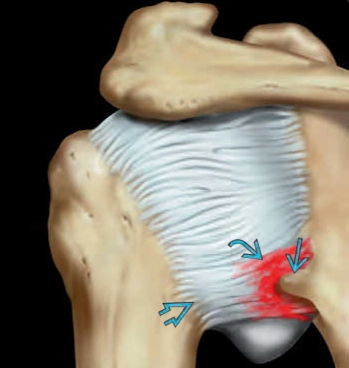

Tổn thương Bankart (Bankart Lesion)/ Rách sụn viền trước dưới